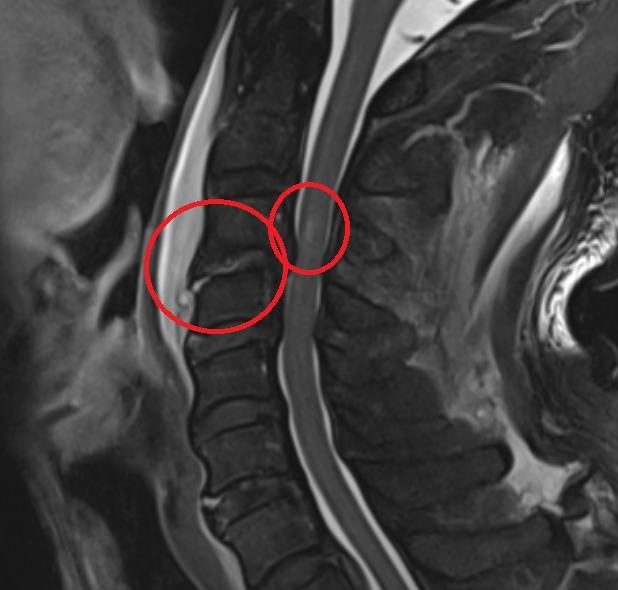

양측 상지의 근력저하가 심하고 하지는 근력저하가 없습니다.

척추 중심관으로 골절은 없는데 디스크 손상에 의한 척수손상에서 수술이 꼭 필요한가요?

근력의 저하가 있고 해당 병변이 원인이라면

네 수술의 필요성이 있을 것 같습니다.